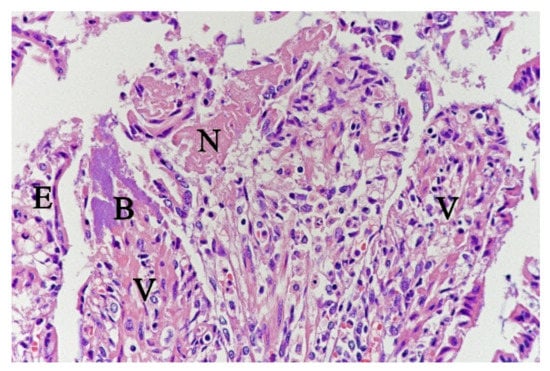

Figure 4.

Histological section from small intestine dog with acute haemorrhagic diarrhoea, HE-stain. There was a loss of surface epithelium, necrotic epithelial cells (N), and elongated/stretched epithelial cells (E) trying to cover lamina propria. Note the abundance of bacteria (B) in a necrotic area on one of the villi (V).

In contrast, the small intestinal mucosa showed dramatic changes with diffuse loss of surface epithelium and loss of architecture with collapse of the villi lamina propria. In some of the dogs, necrosis of intestinal epithelial cells was observed, and multifocal haemorrhages were seen in the deep lamina propria and submucosa (Figure 4). Gram-stained sections showed rich amounts of small Gram-negative rods, located as single bacteria or thick layers close to the surface or as larger clusters deeper in the collapsed lamina propria (Figure 5). Additionally, varying, but often rich amounts of large Gram-positive rods often adherent to the denuded or naked remnants of the villi lamina propria, were observed. The histopathological changes in the large intestine were similar to the findings in the small intestine, with the observation of the same types of bacteria on the surface and in the lamina propria.